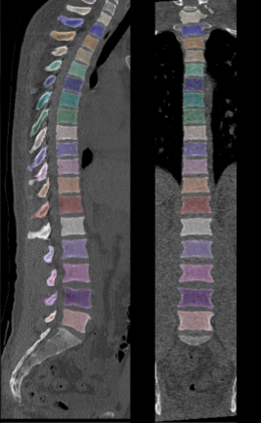

This work proposes a framework for the patient-specific characterization of the spine, which integrates information on the tissues with geometric information on the spine morphology. Key elements are the extraction of 3D patient-specific models of each vertebra and the intervertebral space from 3D CT images, the segmentation of each vertebra in its three functional regions, and the analysis of the tissue condition in the functional regions based on geometrical parameters. The localization of anomalies obtained in the results and the proposed visualization support the applicability of our tool for quantitative and visual evaluation of possible damages, for surgery planning, and early diagnosis or follow-up studies. Finally, we discuss the main properties of the proposed framework in terms of characterisation of the morphology and pathology of the spine on benchmarks of the spine district.